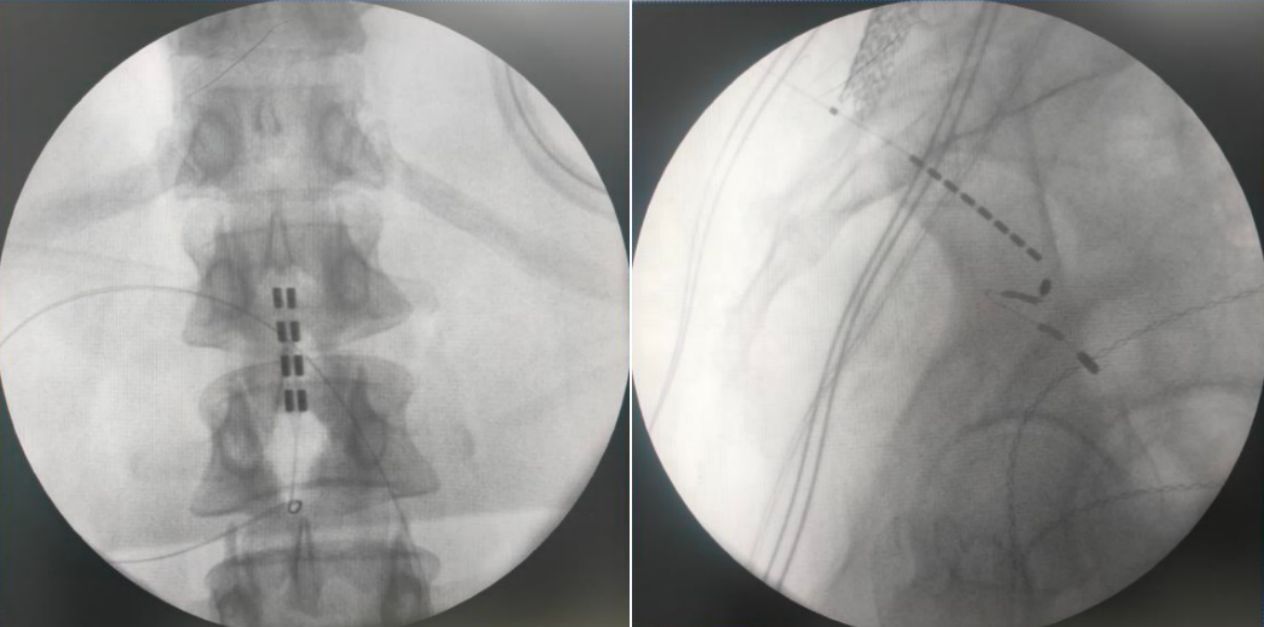

由于该患者为脊髓拴系,脊髓位置偏低,而且脊柱裂合并骶椎骨性解剖畸形给骶孔穿刺带来了非常大的难度,但是通过术前的系统评估以及术中电生理监测,李萃萃主任团队将一根穿刺电极精准置入S3骶孔位置以改善二便功能,另一根4-4排布的片状电极覆盖L1-2节段(患者脊髓低位,放置位置需根据患者情况个性化调整)以调控下肢肌张力异常和感觉障碍。术中测试显示,骶神经刺激可有效引发二便感知,脊髓电刺激则完整覆盖臀部及双下肢。

术后,根据患者实际情况,团队为其制定了个性化程控方案。患者清醒即时测试:骶神经刺激可灵敏感知尿意,脊髓电刺激良好覆盖臀部及双下肢。束带感明显缓解,下肢肌张力明显改善。